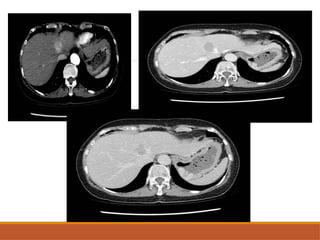

CT SCAN NECT: welldefined round to oval hypo dense mass. CECT: typically shows early peripheral  enhancement. Centre of the tumor remains no enhanced (abundant fibrous stroma). In delayed phase centre of the tumor is enhanced. Capsule retraction and biliary dilatation adjacent to mass is highly suggestive of ICCA.

• #47 Axial cect images showing illdefined infiltrative lesions noted involving segment 4 a and 8 of liver with heterogenous enhambncement in portal vfenous phase There are few peripherally enhancing focal lesions noted adjacent to the above mentioned lesion There is also infiltration of lesion into portal vein Diffuse infiltrative lesion is noted involving subsegment IVa and VIII of the liver, it is ill defined, hypodense with evidence of peripheral enhancement in portovenous phase and becomes smaller in the delayed phase. It is associated with localized intra hepatic biliary radical dilatation at the left hepatic lobe and with mulitple variable size scattered focal lesion at both hepatic lobes showing marginal enhancement. Nevertheless, there is traction on the hepatic capsule at the anterior segment of right lobe and thrombus wtihin the SMV and partially occluding the main PV. Bone window images show two small osteolytic lesions at L3 vertebral body and another one at the right ileum. Lung bases show few subcentimetric pulmonary nodules at the left lower lobe. Simple right renal cyst and minimal ascites are noted.

• #48 Axial plain image showing intrahepatic biliary radicular dilation and illdefine dhypodense lesion in segment 5 On cect in arterial phase the lesion is showing peripheral enhnacenet with retention of contrat in delayed phases IHBRD with retention of contrats in delayed phass indicates cholangiocarcinoma